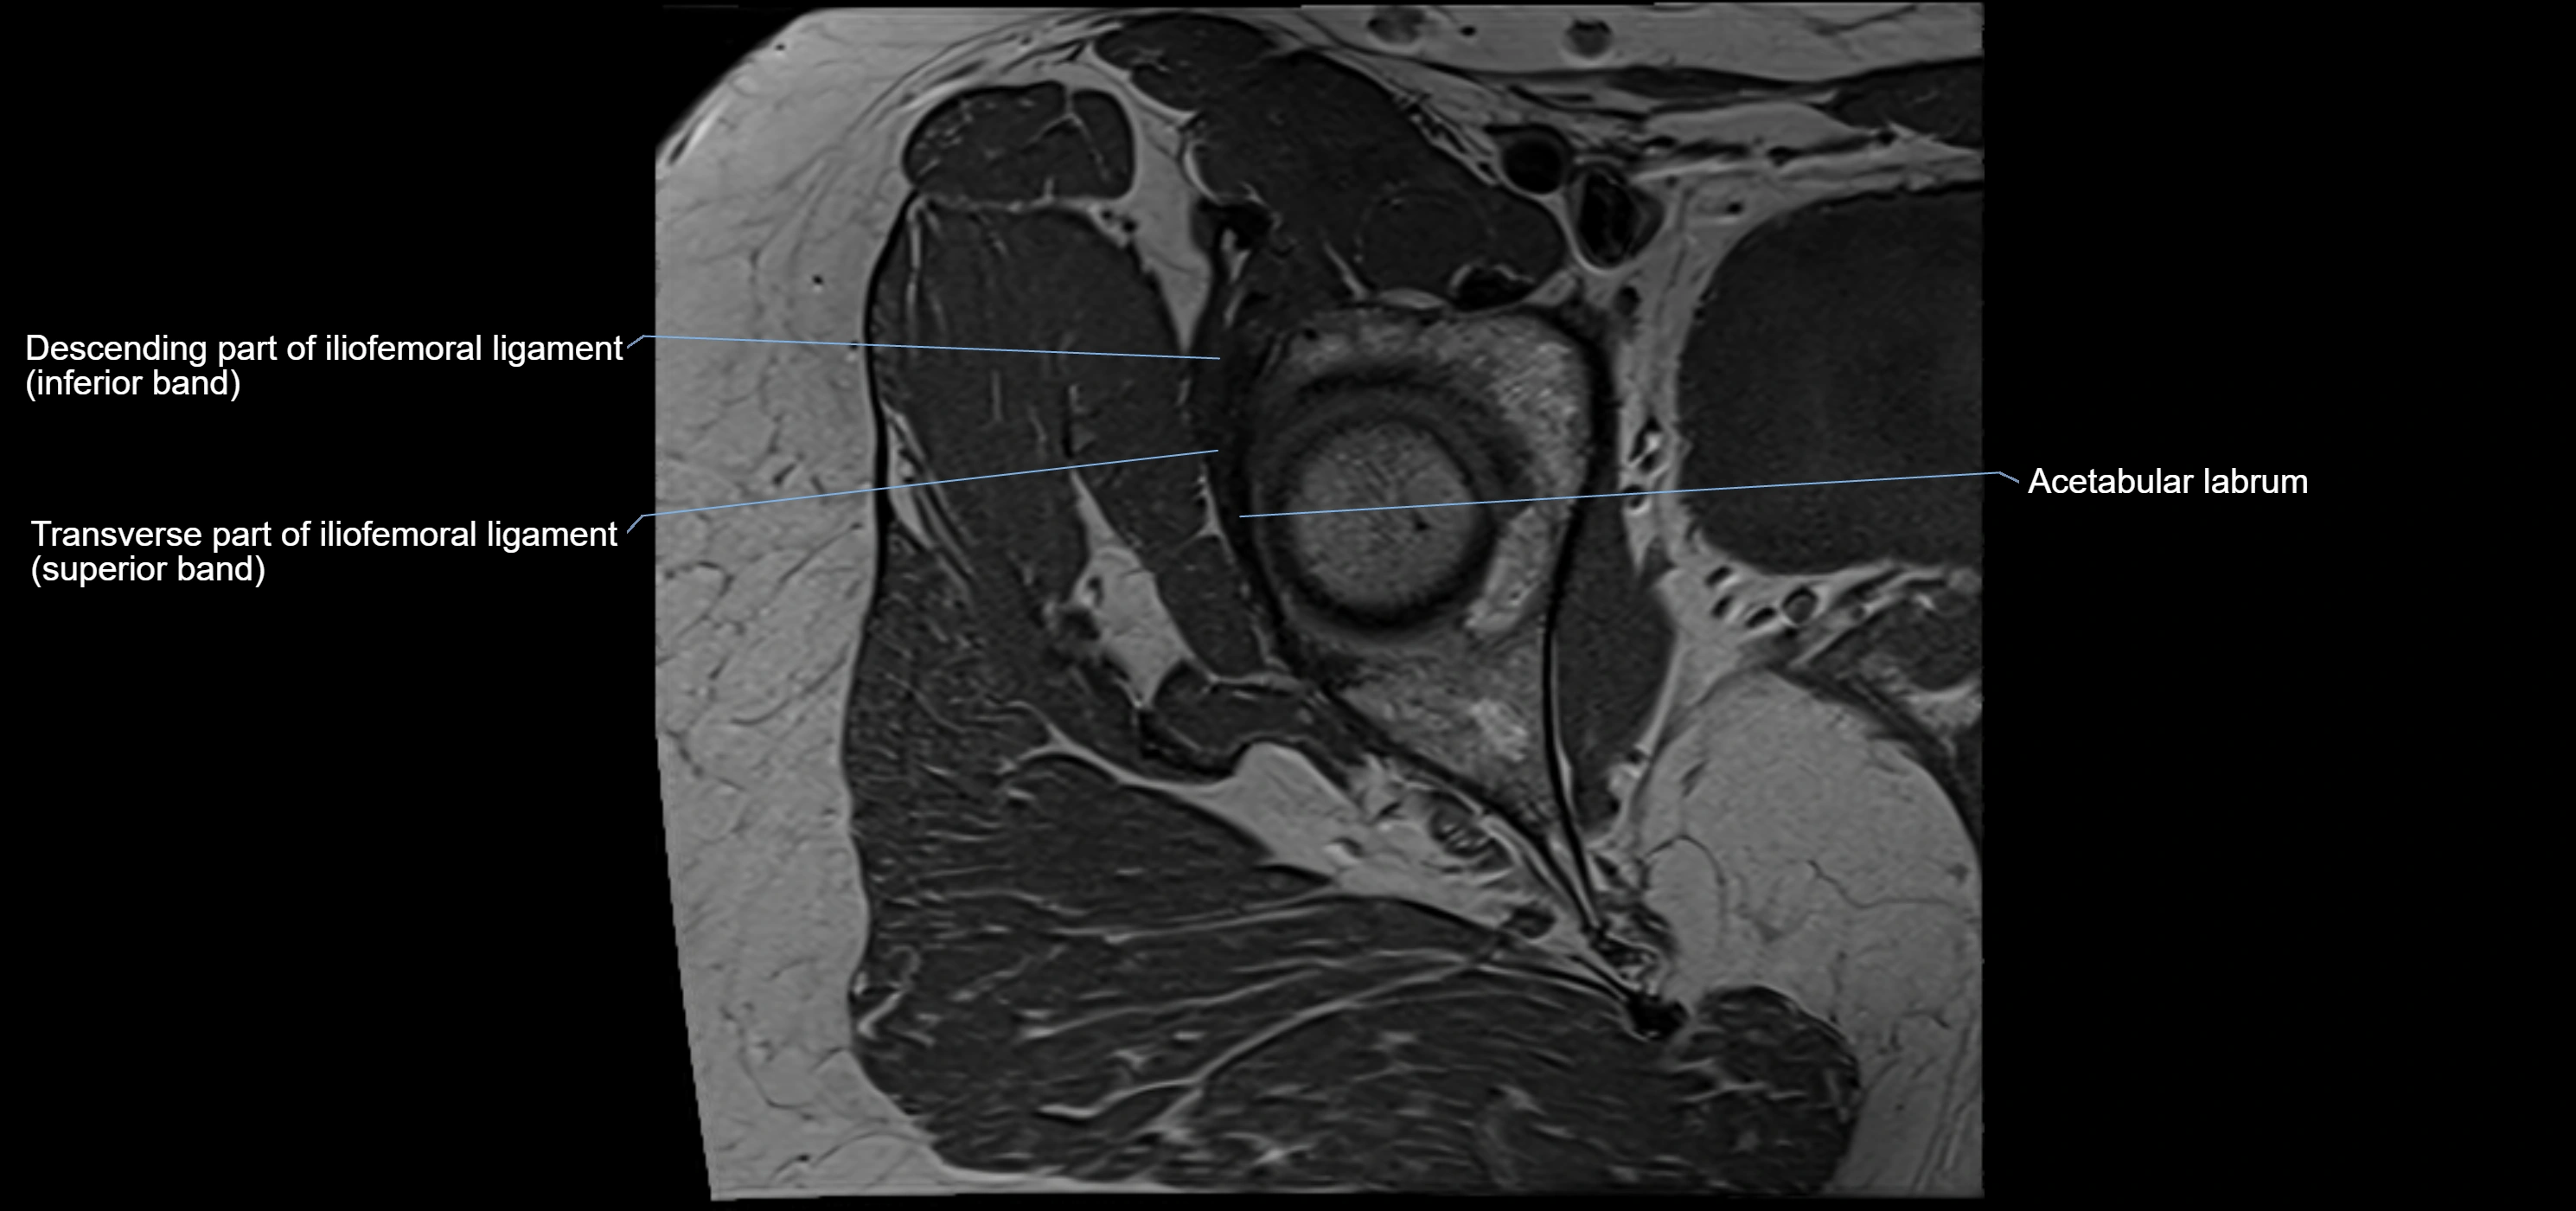

MRI Appearance

T1-weighted images:

• Labrum: low signal intensity (dark)

• Surrounded by intermediate signal joint fluid (bright on arthrogram)

• Tears: linear or focal areas of intermediate-to-high signal interrupting labral continuity

T2-weighted images:

• Joint fluid: bright, making labral tears visible as fluid extending into or around labrum

• Degeneration: may show areas of increased signal within labrum

MRI image

image